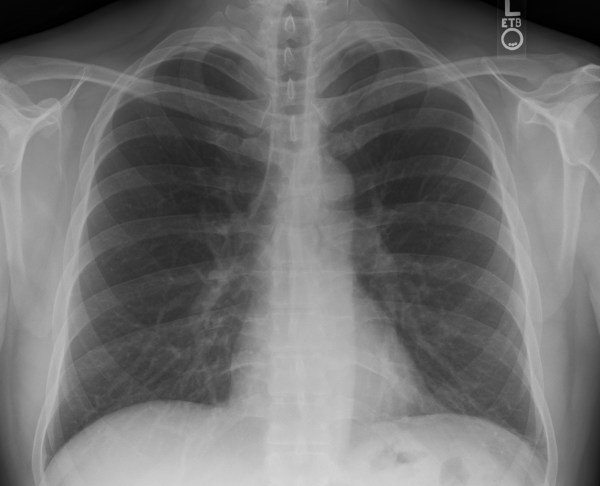

На данный момент в Марий Эл 333 человека лечатся в инфекционных стационарах, 328 из них - с пневмонией. Коронавирус лабораторно подтвержден у  159 пациентов. 58 человек находятся в тяжелом состоянии, пятеро - на искусственной вентиляции легких и 144 пациента  нуждаются в кислородной поддержке.

На утро 4 августа в Йошкар-Олинской городской больнице лечатся 108 пациентов с пневмонией. С подтвержденной коронавирусной инфекцией (КИ) – 92. В тяжелом состоянии – 35 человек, в состоянии средней степени тяжести – 73. Два пациента на ИВЛ, 51 нуждается в кислородной поддержке.

В инфекционном отделении Волжской центральной городской больницы лечатся 46 пациентов с пневмонией. С подтвержденной КИ – 12. В тяжелом состоянии - 6, в состоянии средней степени тяжести – 40. В кислородной поддержке нуждаются 26 человек.

В инфекционном отделении Мари-Турекской ЦРБ на лечении 35 пациентов с пневмонией. С подтвержденной КИ – 4 человека. В тяжелом состоянии 4 пациента, 31 - в состоянии средней степени тяжести. В кислородной поддержке нуждаются 17 человек.

В Звениговской ЦРБ находятся 22 пациента с пневмонией, 1 в тяжелом состоянии, 21 - в состоянии средней степени тяжести. Все нуждаются в кислородной поддержке.

В инфекционном отделении Козьмодемьянской межрайонной больницы лечатся 24 пациента с пневмонией. С подтвержденной КИ – 5. Тяжелых - 7, в состоянии средней степени тяжести – 16, легкой степени тяжести – 1.

В Детской республиканской клинической больнице лечатся 8 пациентов в состоянии средней степени тяжести. 4 - с подтвержденной КИ.

В Медведевской ЦРБ находится 90 пациентов, 89 из них – с пневмонией. 4 - в тяжелом состоянии, 86 - в состоянии средней степени тяжести. 16 нуждаются в кислородной поддержке. С подтвержденной КИ – 38 человек.